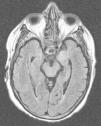

Presentamos el caso clínico de una mujer de 71 años con dislipemia, hipotiroidismo y carcinoma ductal de mama con exéresis radical, y actualmente en tratamiento con quimioterapia. Ingresó en el hospital por sepsis por Staphylococcus aureus meticilin-sensible (por infección del reservorio). Sufre de forma progresiva desorientación, habla repetitiva y somnolencia con evolución a status epilepticus, por lo que ingresó en el servicio de medicina intensiva (SMI). Se realizó tomografía computarizada (TC) craneal urgente, sin hallazgos significativos. A su ingreso presenta estado post-crítico, tras administración de benzodiacepinas intravenosas (IV), y temperatura de 38°C; el resto de la exploración por aparatos resultó normal. En la analítica reseñar plaquetas 22×109/l, creatinina 3,5mg/dl, urea 95mg/dl, proteína C reactiva 15,6mg/dl, resto normal. Se procedió a intubación orotraqueal y realización de punción lumbar (PL) con salida de líquido cefalorraquídeo (LCR) transparente a normopresión sin células, glucosa 68mg/gl y proteínas 64mg/dl (proteínas plasma 5,2g/dl). Se iniciaron sedo-analgesia, fluidoterapia, levetiracetam, tratamiento antimicrobiano IV de amplio espectro, que incluyó aciclovir. Se aislaron en broncoaspirado y un hemocultivo Klebsiella pneumoniae productora de betalactamasas de espectro extendido, sin condensación en la radiografía de tórax; urocultivo y cultivo de LCR negativos. LCR con reacción en cadena de la polimerasa (PCR) para virus de herpes simple (VHS), citomegalovirus (CMV), virus varicela-zóster (VVZ) y virus Epstein-Barr (VEB) negativos, con citología negativa para células malignas. Serologías para virus de la inmunodeficiencia humana, hepatitis, VHS, CMV y VVZ negativas para infección activa. CA 125 elevado (180,3U/ml); resto de marcadores tumorales normales. Anticuerpos (Ac) anti-DNA, antinucleares, c-ANCA y p-ANCA negativos. Hormonas tiroideas en rango dentro de la normalidad con tratamiento sustitutivo y Ac antiperoxidasa y antitiroglobulina negativos. Se realiza nueva TC con contraste que descartó enfermedad estructural, y PL de control con salida de líquido transparente a normopresión con perfil bioquímico normal sin células, y negativo para malignidad. Dado el bajo nivel de conciencia se realiza electroencefalograma (EEG) que es compatible con efecto de la sedación y resonancia magnética nuclear (RMN) cerebral con el siguiente resultado: en la secuencia potenciada en T2 hiperintensidad de la región hipocámpica de predominio izquierdo, en la secuencia en difusión se observa hiperintensidad con discreto descenso del coeficiente de difusión aparente (ADC) en la región hipocámpica del lóbulo temporal izquierdo. Tras la introducción de contraste paramagnético no se observan captaciones (figs. 1 y 2A y B).

Ante los datos clínicos y la neuroimagen característica se planteó el diagnóstico de EL; se solicitaron Ac onco-neuronales en sangre y LCR (frente NMDA, IA-2, GAD, Hu, Yo, Ri, PNMA2, CV2, antifisina, titina, recoverina y SOX1) que fueron negativos. Se inició tratamiento con metilprednisolona IV 1mg/kg/d con recuperación neurológica lentamente favorable. Alta del SMI a los 35 días y del hospital a los 20 días, después tratamiento con prednisona vía oral 1mg/kg/d durante 3 meses, tras los cuales presentó recuperación neurológica «ad integrum».

El cuadro clínico de la EL se caracteriza por la aparición subaguda2 de alteraciones neuropsiquiátricas diversas que incluyen, entre otras, deterioro cognitivo, convulsiones, depresión, irritabilidad, alucinaciones y pérdida de memoria reciente3,4. En la mayoría de los casos el LCR5 muestra cambios inflamatorios con proteinorraquia y/o pleocitosis discretas, sin hallazgos patognomónicos. La TC5 habitualmente es normal, sin captación de contraste y la RMN cerebral5 en el 70% de los casos muestra hiperintensidad de ambos lóbulos temporales en forma asimétrica, especialmente en las secuencias T2 y FLAIR, que no realza con contraste. El EEG puede mostrar lentitud temporal o difusa, espigas temporales, actividad convulsiva focal temporal o generalizada.